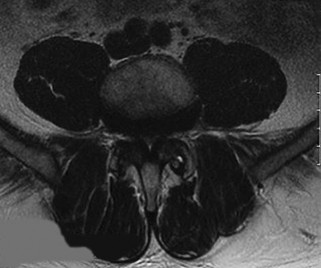

A 60-year-old male with poorly controlled diabetes mellitus presents with severe back pain, fever, and progressive bilateral lower extremity weakness over the past 24 hours. An urgent MRI confirms an anterior epidural abscess at L2-L3.

Blood cultures are drawn. What is the next best step in management?